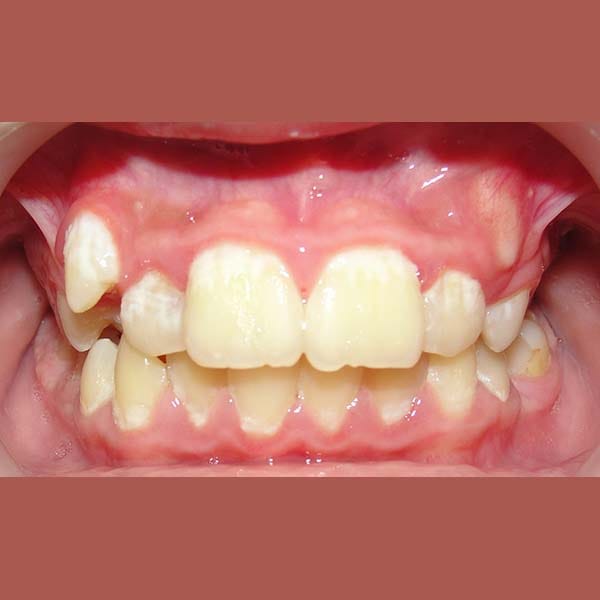

AFTER